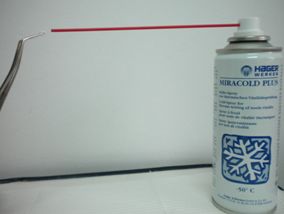

Fig. 3. Test térmico. Estimula fibras A-Delta. Se aplica una torunda de algodón en 1/3 cervical con gas de Diclorodifluorometano (-40º a -50º)